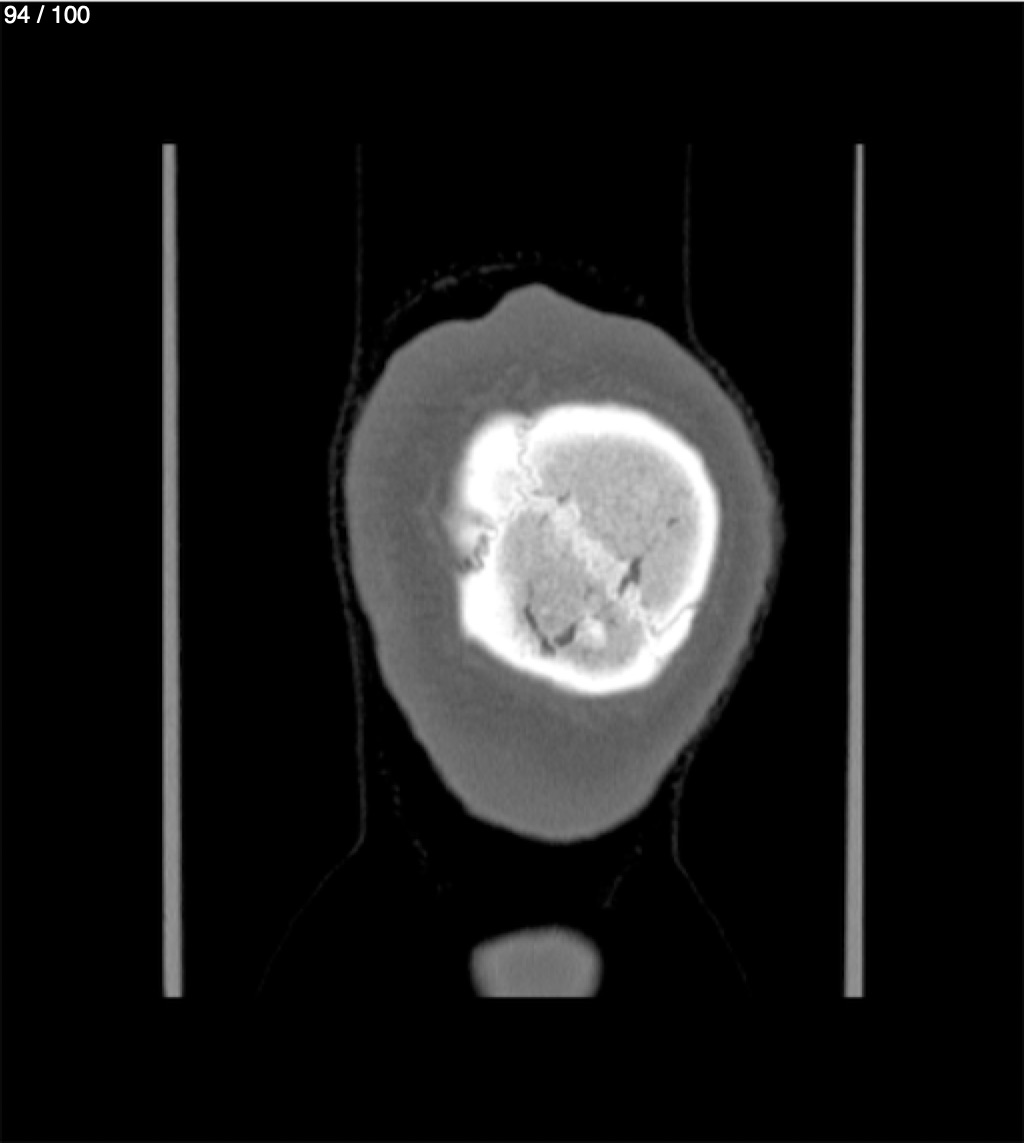

Yonelly Barrios Diaz 35A - T.C Craneo